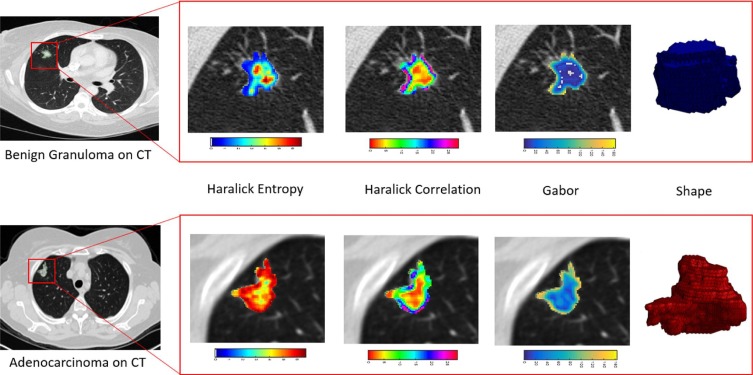

Radiomics & Radio-genomics

Precision-based characterization of solid tumor Prognostic signatures Prediction of metastatic spread and early recurrence Early cancer detection Hallmarks of cancer

Tumor volume measurement 3D cardiac/coronary analysis 3D body imaging 3D musculoskeletal imaging 3D breast imaging 3D nuclear medicine and PET